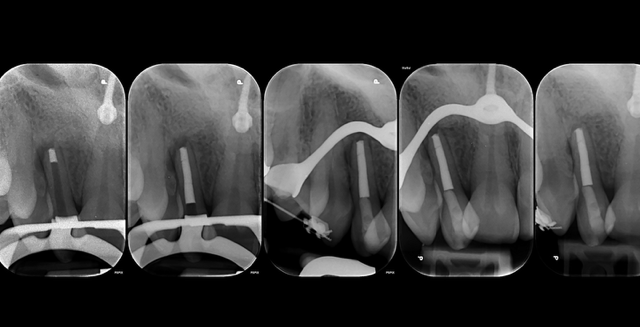

Il ritrattamento endodontico rappresenta una procedura fondamentale per la gestione di denti con fallimento della terapia endodontica primaria. Le cause principali di insuccesso possono essere legate a infezioni persistenti, fratture radicolari, o errori tecnici durante il trattamento iniziale. L’obiettivo del ritrattamento è garantire una completa decontaminazione del sistema canalare, risolvere le infezioni e favorire la guarigione dei tessuti periapicali. Questo intervento, sebbene altamente efficace, comporta sfide tecniche significative, tra cui la difficoltà nell’accesso ai canali radicolari precedentemente trattati, la rimozione di materiali di otturazione, la gestione della curvatura radicolare e la preservazione della struttura dentale residua. L’utilizzo di tecnologie avanzate, come la microscopia operativa, i laser e le apparecchiature per la localizzazione dei canali, ha migliorato notevolmente la precisione e l’efficacia di queste procedure. Durante la relazione verranno discussi i criteri di selezione dei casi da sottoporre a ritrattamento, le tecniche moderne per il trattamento delle infezioni persistenti e le prospettive future in termini di materiali e approcci terapeutici. Sarà inoltre esplorato l’importante ruolo della diagnosi clinica e radiografica per determinare il successo del ritrattamento, così come le implicazioni per la prognosi a lungo termine del dente ritrattato endodonticamente. Il ritrattamento endodontico, pur essendo una procedura complessa, offre una valida soluzione per il salvataggio dei denti compromessi, con ottimi tassi di successo quando eseguito da professionisti esperti e con tecnologie all’avanguardia.

• Rimozione gutta percha e carrier based

• Gestione dei gradini

• Blocchi apicali e false strade.